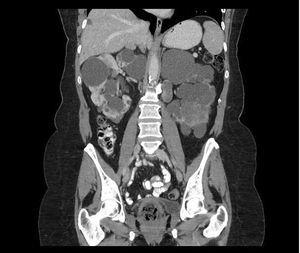

Análisis recientes de la población del estudio CRISP (Consortium of Imaging Studies to assess the Progression of Polycystic Kidney Disease) revelaron que los riñones de pacientes con mutaciones en PKD1 tenían un tamaño dos tercios mayor que los de los pacientes con mutaciones en PKD2 de la misma edad; el tamaño renal estaría asociado con la gravedad de la enfermedad. La mayor gravedad de los pacientes con PKD1 se debería al desarrollo de un número mayor de quistes a una edad más temprana y no a una mayor velocidad de crecimiento de los quistes (figura 1 A y B)6. Un mayor número de quistes en PKD1 a una edad más temprana concuerda con un modelo two-hit de quistogénesis, porque el gen PKD1 es un blanco mayor para las mutaciones. En este modelo, se hereda un gen PKD1 o PKD2 mutado de un progenitor y un gen normal del progenitor no afectado. En una segunda etapa, el gen normal sufre una mutación somática y queda, de esta manera, desactivado.

Figura 1. Imagen de resonancia magnética en 2 pacientes de 48 años de edad con mutaciones en PKD1 (A) y PKD2 (B).